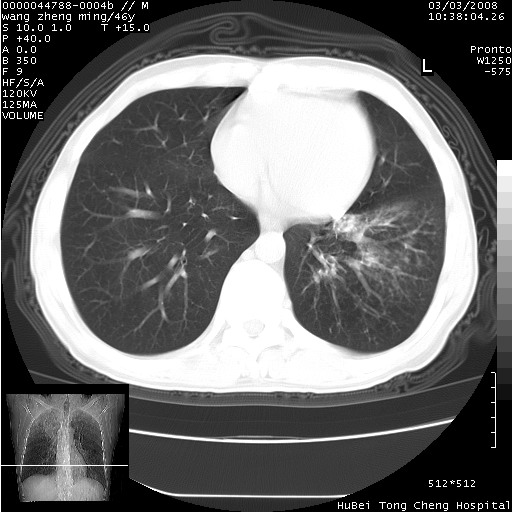

以下是引用卜一在2008-3-22 1:37:00的发言:[br]右肺实质性肿块,边缘不整,明显见毛刺征 分叶征及胸膜凹陷征,右上叶支气管明显变窄,远端散在的片状 斑片状实变影。另:左肺门较大肿块,支气管受累 变窄,远侧见阻塞性肺炎。纵隔内见肿大淋巴结。多考虑:右肺周围性肺癌伴左肺门 纵隔淋巴结转移!